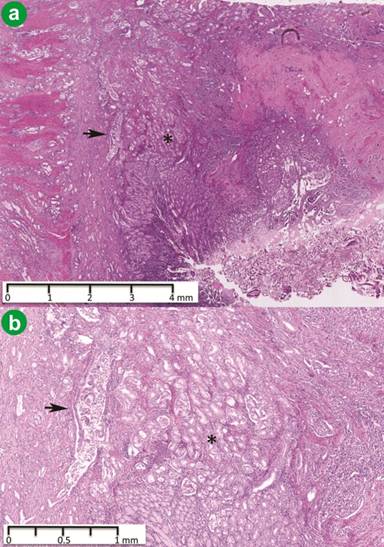

Macroscopically, the ampulla contained a tumor measuring 35 mm in maximum dimension that infiltrated into the head of the pancreas with extensive surrounding necrosis. Histopathological examination revealed a well differentiated adenocarcinoma (T3 N0 M0) composed of angulated glands with pleomorphic nuclei (Figure 2). An adjacent cluster of glands composed of cells with ovoid nuclei, coarse ‘salt and pepper’ cytoplasm and eosinophilic cytoplasm characteristic of endocrine tumors was also identified (Figure 2). Scattered psammoma bodies were interspersed among the endocrine glands (Figure 3). The endocrine glands infiltrated into the submucosa and measured 10 mm in greatest dimension (T1 N0 M0). The neuroendocrine tumor stained positively for somatostatin (Figure 3). Immunohistochemistry, with positive staining for synaptophysin and a Ki-67 index of less than 1%, confirmed the diagnosis of a Grade 1 endocrine tumor. The endocrine tumor was negative for the epithelial marker BerEP4 in contrast to the strongly positive adenocarcinoma (Figure 3). Staining for peptide hormone content of the endocrine cells showed somatostatin production with no staining for insulin or gastrin.

Figure 2. a. Endocrine tumor (*) with adjacent adenocarcinoma invading into muscularis propria (arrow) (hematoxylin and eosin stain ×25). b. Endocrine tumor (*) with adjacent adenocarcinoma (arrow) (hematoxylin and eosin stain ×50). |